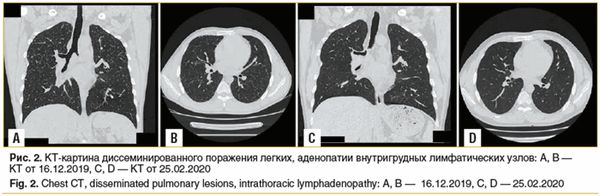

Данные обследования: КТ органов грудной клетки от 16.12.2019 — очаговая диссеминация по всем легочным полям с обеих сторон. Аденопатия верхнего отдела центрального средостения. В динамике: с 12.07.2019 по 16.12.2019, по данным ПЭТ и КТ, — нарастание легочного компонента. Заключение: диссеминированное поражение легких, прогрессирующее течение. Аденопатия внутригрудных лимфатических узлов (рис. 2 А, В).

На КТ 25.02.2020 (рис. 2 C, D) по сравнению с данными от 16.12.2019 отмечается практически полная регрессия мелких элементов диффузного поражения легких равномерно во всех отделах, а также уменьшение и нормализация размеров лимфоузлов паратрахеальных групп и аортопульмональной и бифуркационной группы.